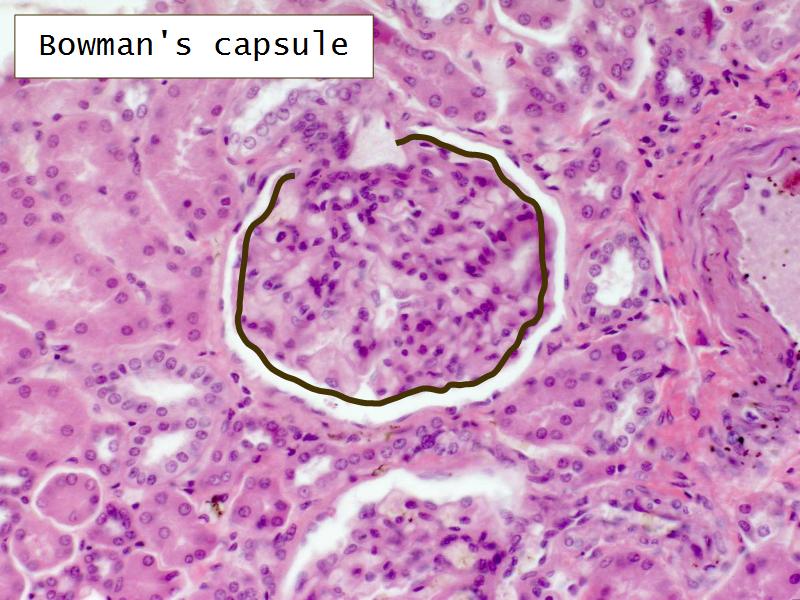

- The renal corpuscle

- Complete the drawings for each slide in the practical workbook.